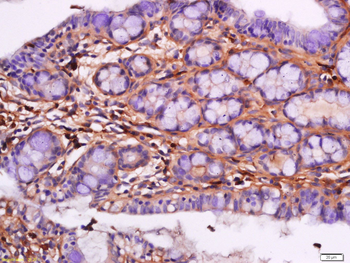

10 μg, 100 μgChemerin Rabbit Polyclonal Antibody [orb156351]

IF, IHC-Fr, IHC-P

Bovine, Porcine

Human, Mouse, Rabbit, Rat

Rabbit

Polyclonal

Unconjugated

100 μl, 200 μl, 50 μlGoat anti-CYP26B1 Antibody [orb19329]